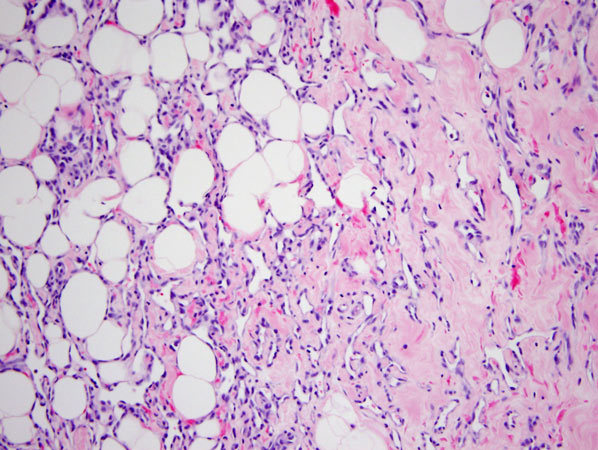

Primary (de novo) angiosarcoma of the breast

Secondary (radiation-associated) angiosarcoma

APRVP

Stains?